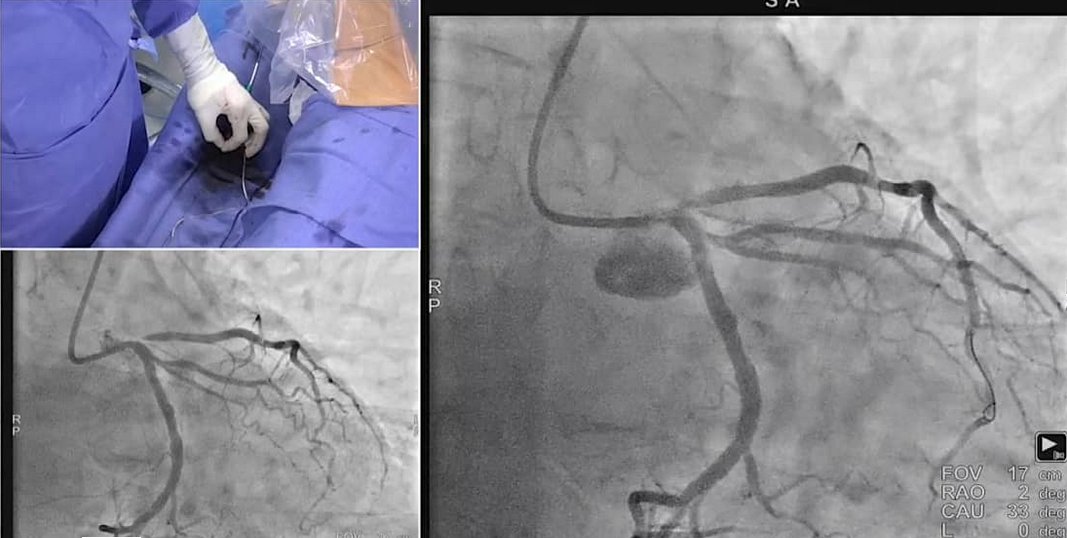

50 yrs M, NSTEMI, CAG+IVUS-significant LM & LAD disease/ LCx dominant & disease free. 3.5x26 onyx LM-lad & POT with 4.5x12NC. Final angio significant pinching of dominant lcx. What next u will do?

#cardiotwitter#RadialFirst@aayshacader@mmamas1973@mirvatalasnag@DLBHATTMDpic.twitter.com/isvMmSr6PxPrikaži ovu nitHvala. Twitter će to iskoristiti za poboljšanje vaše vremenske crte. PoništiPoništi -

CHIP at its best with my mentor

@KhalidTammam#cardiotwitter#RadialFirst#cto@PCRonlinepic.twitter.com/GJsmROWoXEHvala. Twitter će to iskoristiti za poboljšanje vaše vremenske crte. PoništiPoništi